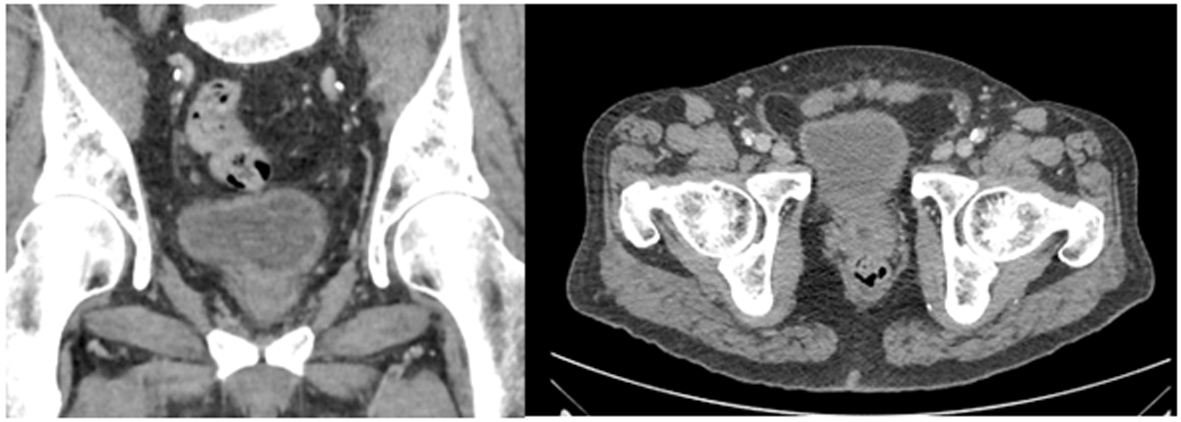

Xanthogranulomatous Prostatitis Presenting as a Prostatic Abscess: Case Report and Review of Literature

Figures